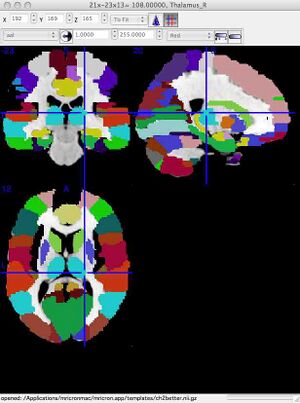

Teaching Aid: Colored Overlay to show different anatomical regionsWhile the above co-ordinates show examples of single locations and their label, it can also be nice to see the complete extent of an area. This can be done as follows:

Surf around the brain. When clicking on a colored region, you will see the anatomical label for that colored area of the brain. The label (e.g. Putamen_L for left putamen) will appear in the bottom of the viewing window on PC, in the top of the viewing window on Mac. OPTIONAL Step 3: Different kinds of brain MRIMRI is clinically very useful because it is non-invasive and safe. Because no exposure to radiation is involved, patients can receive many different kinds of MRI imaging procedures without risk. The MRI scanner can be programmed to create different kinds of images that reveal different tissue properties. The three main kinds of images are T1, T2 and Proton Density (FLAIR). The names of the image types refer to the physical priniciples used to create the images. The three links below link to three datasets, all collected from the same normal subject, that show the three different image types. Click on each link and save the file to your computer.